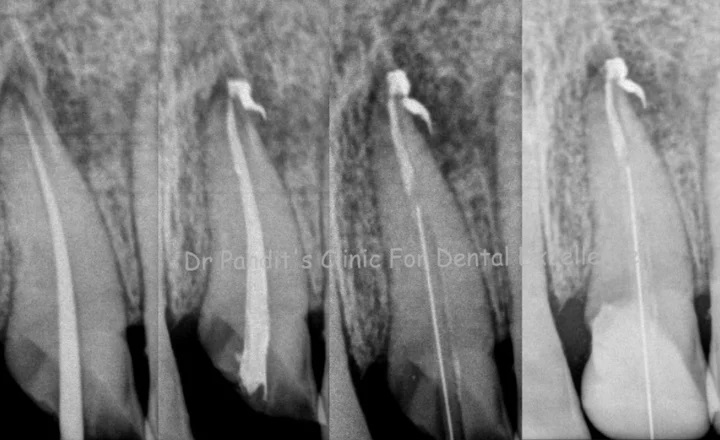

Root canal treatment removes infected tissue and the damaged nerve from inside the tooth, eliminating pain and preventing reinfection. It is a far better option than tooth extraction, as no artificial replacement matches a natural tooth.

In retreatment, infected canals are cleaned, disinfected, and sealed again. In rare cases, an apicoectomy may be recommended to remove the root tip.

Microscopic Endodontic Treatment

Microscopic endodontics enhances precision by magnifying the treatment area up to 25 times, leading to better diagnosis and outcomes.

• Identifying hidden and accessory canals

• Removing separated instruments

• Preserving maximum tooth structure